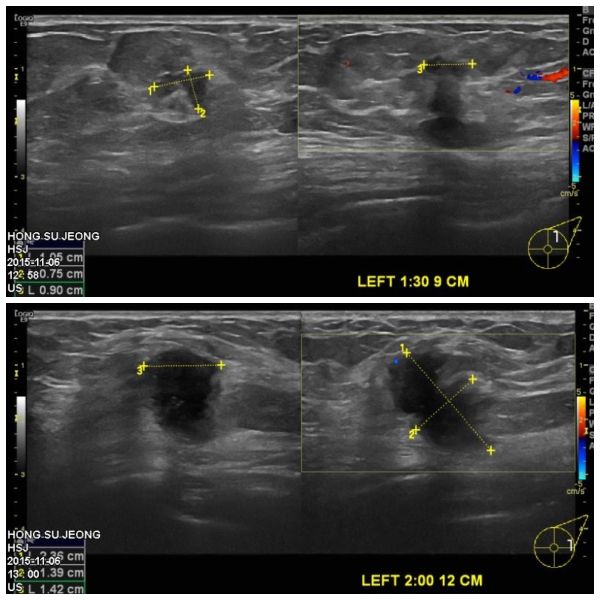

좌측유방에 만져지는 멍우리로 내원하신 70대 환자분이십니다.

유방초음파상 확인되는 좌측유방에 2개의 혹을 조직검사 시행하였고

결과상 2개 혹 모두 침윤성유관암으로 진단되었습니다.